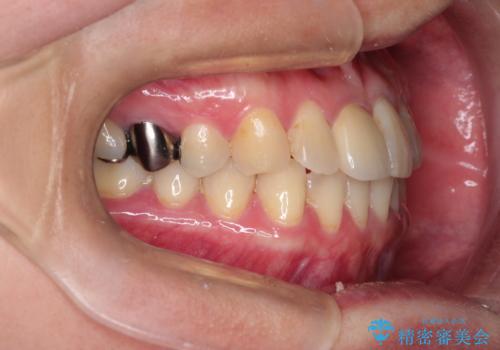

- 前歯の歯並びが気になるとのことで来院されました。

右上の1番目の歯が内側に入り込んでしまっており、その歯がの先端がすり減ってしまっていました。

インビザラインによる矯正治療で前歯の歯並びを改善し、セラミッククラウン装着により歯の形態の回復をする計画としました。